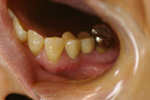

50代女性の症例

【治療前】

・見た目をきれいにしたい

・歯を長持ちさせたい

とご希望がありインプラント治療を行いました。